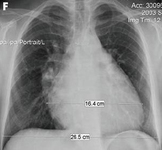

Ressonância nuclear magnética em um paciente com regurgitação pulmonar após reparo de tetralogia de Fallot. O paciente tem ventrículo direito não restritivo e o coração é grande

De: Chaturvedi RR, Redington AN. Heart. 2007 Jul;93(7):880-9; usado com permissão